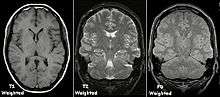

Contrast

Image contrast may be weighted to demonstrate different anatomical structures or pathologies. Each tissue returns to its equilibrium state after excitation by the independent processes of T1 (spin-lattice) and T2 (spin-spin) relaxation.

To create a T1-weighted image, magnetization is allowed to recover before measuring the MR signal by changing the repetition time (TR). This image weighting is useful for assessing the cerebral cortex, identifying fatty tissue, characterizing focal liver lesions and in general for obtaining morphological information, as well as for post-contrast imaging.

To create a T2-weighted image, magnetization is allowed to decay before measuring the MR signal by changing the echo time (TE). This image weighting is useful for detecting edema and inflammation, revealing white matter lesions and assessing zonal anatomy in the prostate and uterus.

The standard display of MRI images is to represent fluid characteristics in black and white images, where different tissues turn out as follows:

| T1-weighted | T2-weighted | |

|---|---|---|

| Bright |

|

|

| Inter- mediate | Gray matter darker than white matter[102] | White matter darker than grey matter[102] |

| Dark |

|

|